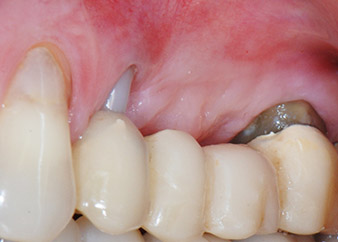

Mujer de 58 años de edad, que además es una apreciada colega y amiga, y se quejaba de dolor y de un aumento en la movilidad del pilar del puente de la pieza dental 24. También había inflamación periodontal, con bolsas de una profundidad de 7 mm en sentido mesiobucal y más de 12 mm en sentido distal, así como furcación de tercer grado. Asimismo, la radiografía reveló una lesión periodontal extensa alrededor de la región apical de la pieza dental 24 (figura 1) tratada previamente con endodoncia (alio loco).

Un año antes, las piezas dentales 25 y 26 se habían extraído por razones traumáticas y endo-periodontales antes de la colocación del puente. Se diagnosticó una lesión endo-periodontal combinada en la pieza dental 24, pero su componente etiológico principal no estaba claro. La paciente declaró su voluntad de mantener el pilar del puente de las piezas 24 y 27 y afirmó que no aceptaría una prótesis extraíble final, ni siquiera provisional. Por lo tanto, se acordó intentar por todos los medios conservar ambos dientes, a pesar del mal pronóstico que mostraban las pruebas radiológicas y clínicas.

Después de la medicación tópica con un 25 % de gel de metronidazol (Elyzol) en las bolsas de la pieza 24, se inició un tratamiento causal de terapia periodontal con desinfección de toda la boca. El tratamiento ortógrado del canal radicular se revisó mediante una obturación con gutapercha termoplástica, un poste de fibra de vidrio y una acumulación de núcleo de composite (figura 2). El puente se recementó fuera de la oclusión para permitir la cicatrización sin problemas de los lugares de la GTR y la GBR.